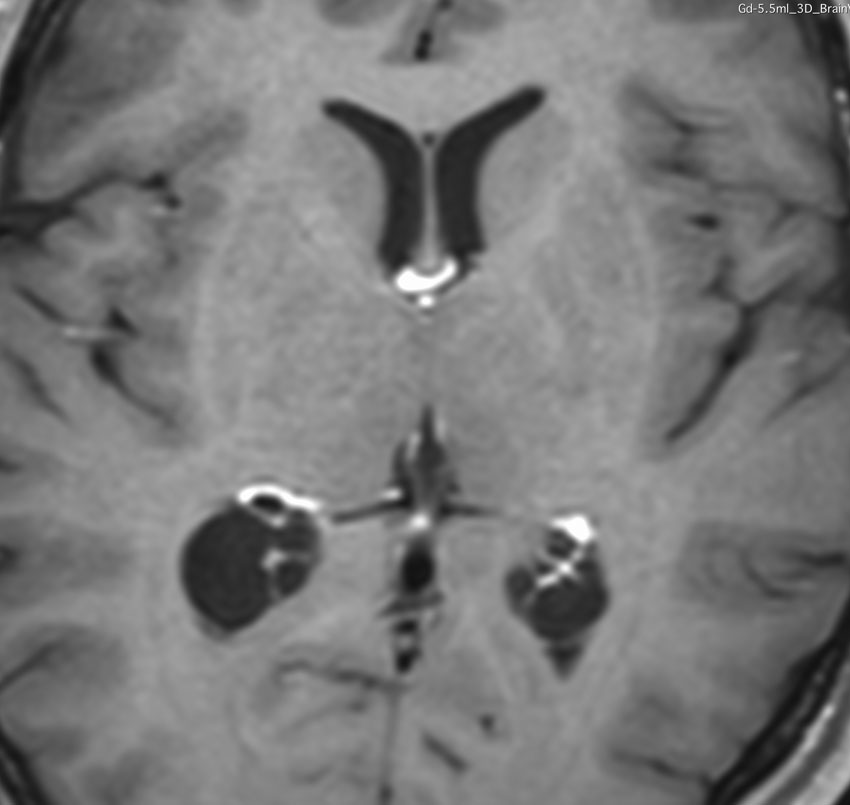

これも側脳室三角部の両側性の脈絡叢のう胞です。ガドリニウム増強で,脈絡叢が固まっていなくてばらけたように見えます。